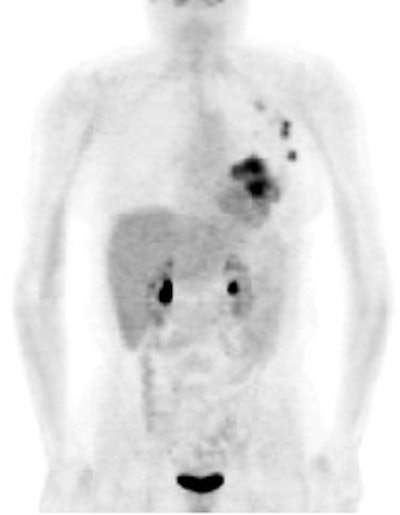

Monitoring response to therapy: The patient shown below had received chemotherapy for treatment of metastatic breast cancer (pre-therapy scan is on the left). The post-therapy scan (right image) demonstrated a very good response to treatment, however, several foci of tracer uptake remained (black arrows) consistent with residual metastatic disease. Further therapy was planned as a result of the PET scan. |

|